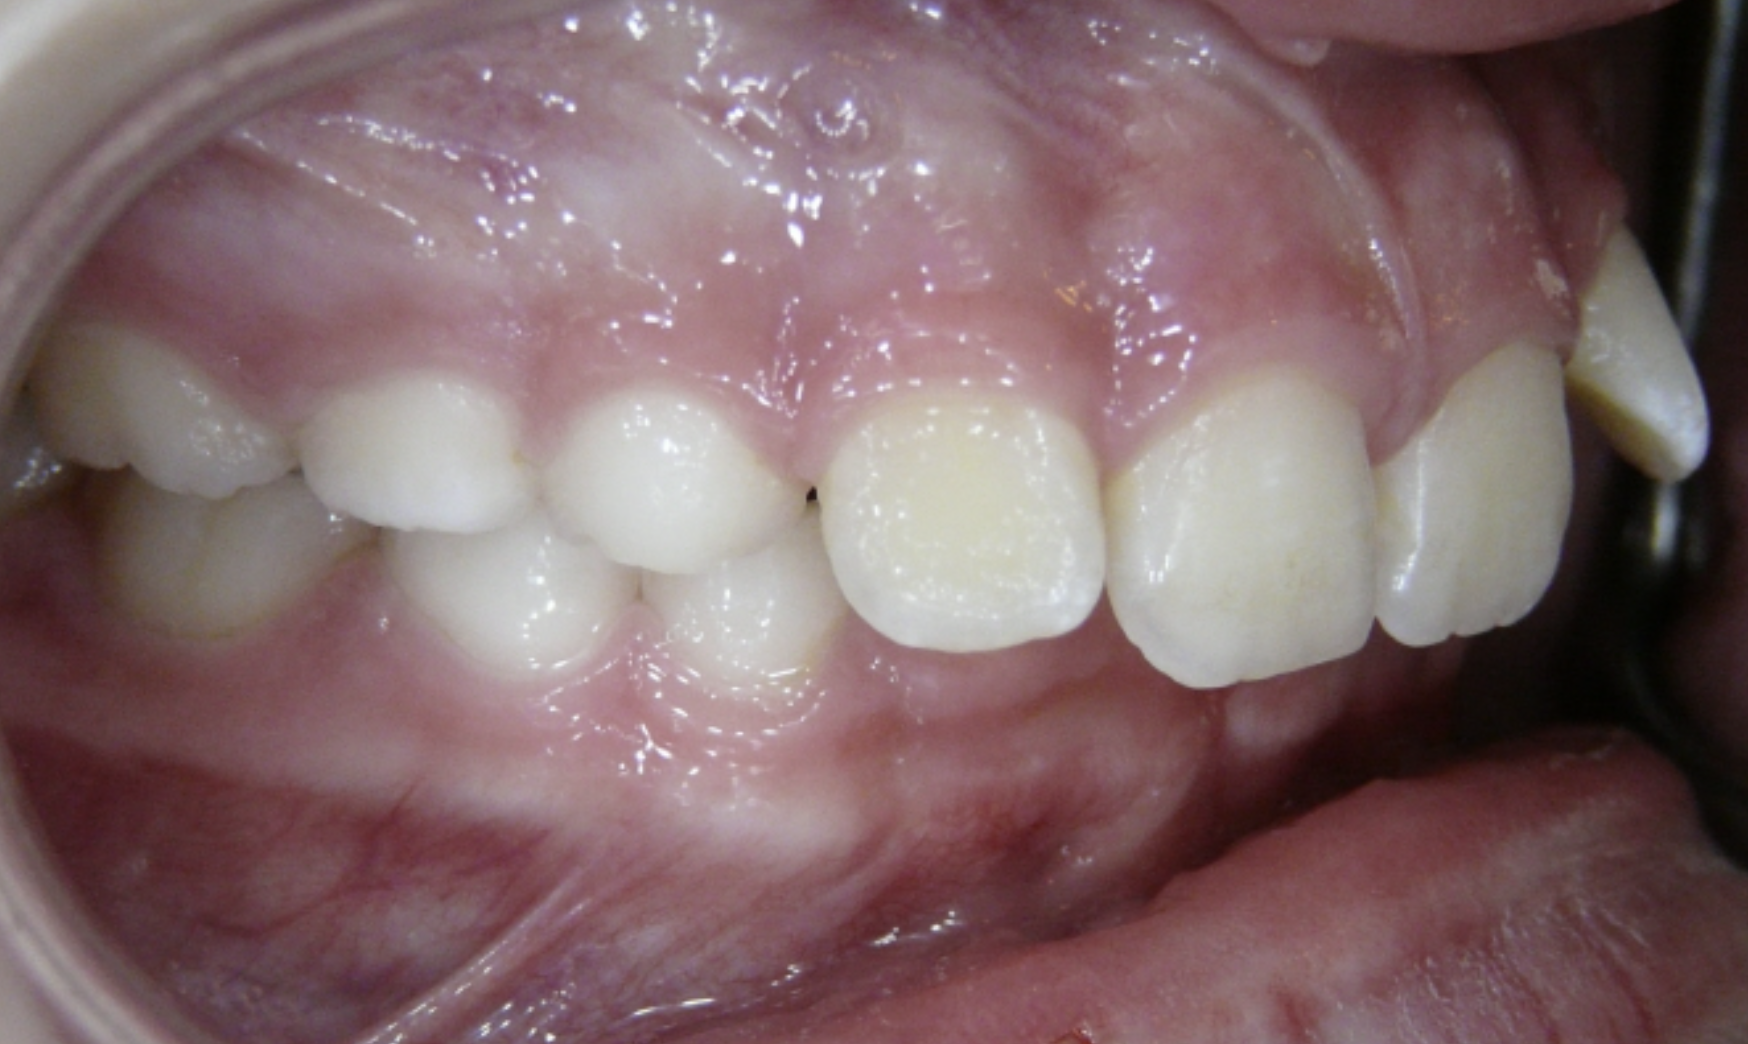

Underbite

Lower teeth sit in front of upper teeth when back teeth are closed.